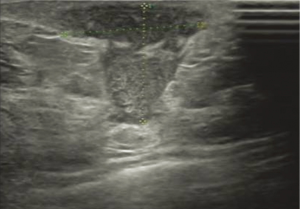

All of 178 patients had breast mass with unclear boundaries, ranging from 2~14 cm in diameter. Of them, 134 patients (75.3%) complained of skin ulcerations and swelling (Figure 1), 127 (71.3%) with abscesses (Figure 2), 18 (10.1%) with peau d’orange sign, which was easily confused with breast cancer (Figure 3), 6 (3.4%) with skin erythema on legs.

USG showed ill-defined, hypoechoic, heterogeneous lesions in most of the patients with GLM. Sometimes the breast lesion had specific signs including ‘Funnel sign’, ‘tunnel sign’ or ‘quicksand sign’, while it complicated with abscesses (Figures 4-6). According to the previous experience (5,11), 26 patients underwent mammography in our early study, which did not show characteristic signs of the lesion. In late study, patients did not had mammography as a routine examination because of its limitations such as the aggravation of the pain after mammography.